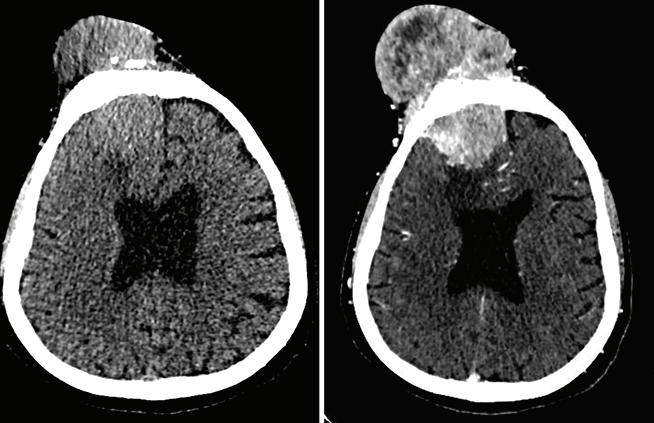

Figura 3: Tomografía con y sin contraste endovenoso realizada 2 años después de la resonancia. En región frontal se observa lesión expansiva, de densidad de partes blandas, que se extiende hacia ambos lados de la calota, que invade la fosa frontal anterior derecha y el seno frontal adyacente con intenso realce tras la administración del contraste endovenoso de tipo heterogéneo compatible con una lesión hipervascularizada. Osteólisis del hueso frontal con patrón permeativo, asociado a áreas de esclerosis óseas con reacción perióstica y remodelación del hueso que se extiende hasta la región del seno frontal y de celdillas etmoidales anteriores. En el parénquima encefálico se observa edema en hemisferio derecho en región frontal y efecto de masa desviando la línea media en la región anterior hacia la izquierda. Servicio de Tomografía de Diagnóstico por imágenes, Hospital de Clínicas “Jose de San Martin”, 2021.